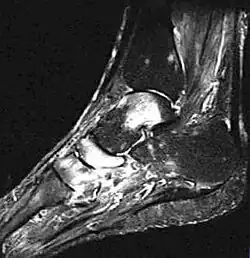

- Fuß, MRT, T2-Gewichtung

-

Zum Vergleich: Sprungbein, Kahnbein und Keilbein unauffällig